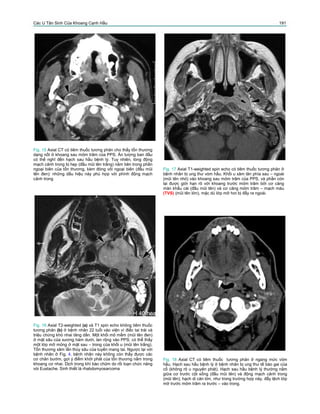

Fig. 9 Axial T2-weighted spin echo ở bệnh nhân 11 tuổi, vào viện

vì đau mặt, chủ yếu khi nhai, giảm thính lực bên phải và sụt cân.

Một khối u lớn (dấu sao) có trung tâm ở PPS bên phải, lan rộng

vào lòng vòm hầu (mũi tên trắng). Khối u đẩy lệch các cơ nhai

(đầu mũi tên đen). Có thể thấy tổn thương xâm lấn khoang

trước cột sống (đầu mũi tên trắng) và đỉnh xương đá bên phải

(mũi tên đen). Sinh thiết cho kết quả embryonal

rhabdomyosarcoma

Fig. 10 Bệnh nhân nhi vào viện vì phù quanh hạnh nhân. Axial

T2-weighted spin echo cho thấy một khối dạng nang ở khoang

trước mỏm trâm của PPS, đẩy lệch thành hầu. Nang được cắt

bỏ và kết quả giải phẫu bệnh là nang khe mang

Schwannomas thường xuất phát từ thần kinh lang

thang. Thoái hóa ác tính hiếm được báo cáo (Al Otieshan

et al. 1998). Biểu hiện MR điển hình của schwannoma là

khối u hình bầu dục hơi tăng tín hiệu trên T2; tổn thương

có thể không đồng nhất do những vùng xuất huyết hoặc

thoái hóa nang. Sau khi tiêm thuốc tương phản, tổn

thương bắt thuốc tương phản mạnh và có thể chẩn đoán

nhầm với những u tăng sinh mạch máu. Thực ra,

schwannoma là tổn thương tương đối giảm mạch máu và

bắt thuốc là do rò rỉ ngoài mạch máu do tính thấm thành

mạch bất thường với những hồ dẫn lưu tĩnh mạch (Fig.

12).

Hiếm gặp hơn, có thể thấy flow voids ở schwannoma

ngoài sọ, tương ứng với các mạch máu dãn bất thường

(Kato et al. 2010); điều này có thể gây nhầm lẫn với

paraganglioma, là u tăng sinh mạch máu, với hình ảnh

flow voids tương ứng với những động mạch nuôi hoặc